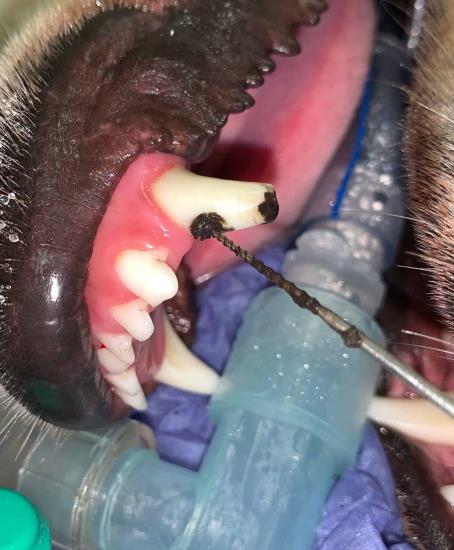

5. Pulp exposure in a canine tooth fracture

Here we have a one month old complicated crown fracture of a canine tooth. This fracture involves enamel, dentin and exposes the sensitive pulp.

Pulp exposure is both painful and opens the pulp to bacteria. Pulpitis and eventually, pulp necrosis will have occurred as a result of this trauma.

Endodontic treatment was performed to remove the black necrotic pulp and enable the patient to keep this strategic tooth. Without treatment these cases can develop into potentially destructive abscesses.